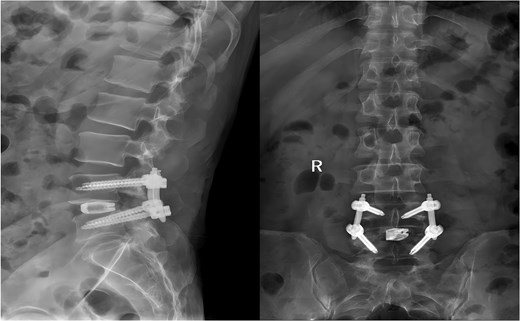

Following removal of the left L5 pedicle screw during the procedure, the smallest endoscopic sheath was inserted along with the endoscope to explore the screw trajectory. Under fluoroscopic guidance, endoscopic forcep was utilized to identify and grasp the fractured guidewire (Fig. 4). Tactile feedback of a metallic sensation confirmed precise localization. Approximately 6 mm of the fractured guidewire was successfully extracted (Fig. 5). Subsequent fluoroscopy confirmed complete removal of the broken guidewire. The left L5 pedicle screw was reinserted, and bilateral connecting rods were placed. The nuts were then securely fastened. Hemostasis was confirmed under endoscopic visualization, and the surgical incisions were closed and dressed with sterile coverings.

Following the surgery, the patient remained in stable condition with no reported discomfort. Postoperative radiographs verified complete extraction of the guidewire, with no residual fragments observed at the fracture site (Fig. 6). The patient experienced an uneventful recovery, and subsequent follow-up evaluations demonstrated satisfactory outcomes.

Postoperative anteroposterior and lateral radiographs of the lumbar spine.